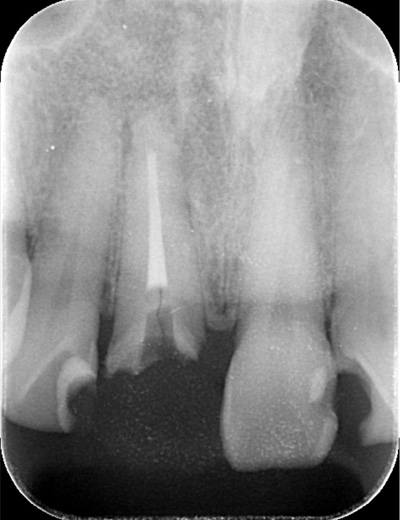

AFTER

| 年代・性別 | 50代 男性 |

|---|---|

| 主訴 | 右下の歯がないのでインプラントをして欲しい |

| 治療期間 | 約6ヶ月 |

| 費用 | 600,000円 |

| 治療内容 | インプラント、骨造成、結合組織移植、セラミック修復 |

| 治療に伴うリスク | インプラント周囲炎 セラミックの破折、脱離 |

*キャンセルポリシーをご一読のうえご予約ください